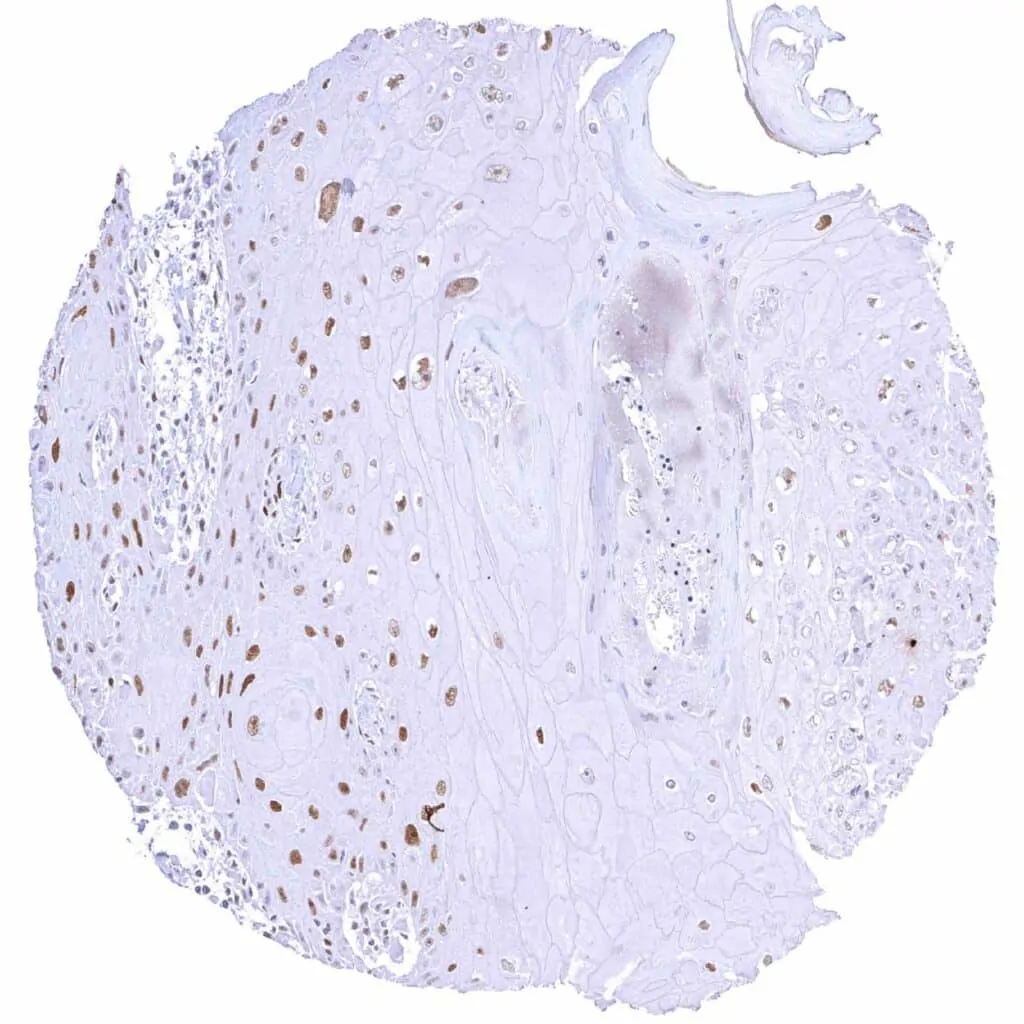

Breast – Invasive breast cancer of no special type (NST) with faint Cyclin E1 immunostaining of few tumor cells